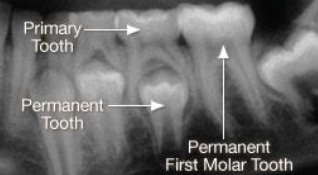

<p><span><strong>How to use the differences in identifying the dentition in </strong></span><strong>radiographs: start with the roots&nbsp;</strong></p>

How to use the differences in identifying the dentition in radiographs: start with the roots

knowt flashcard image

<p><span><strong>How to use the differences in identifying the dentition in </strong></span><strong>radiographs: look at the pulp</strong></p>

How to use the differences in identifying the dentition in radiographs: look at the pulp

Key differences to identify primary vs permanent dentition

 Enamel and dentin are thinner in primary

 Pulp chamber is wider

 Pulp horn is more prominent

 Smaller root trunk for primary

<p><span><strong> Enamel and dentin are thinner in primary </strong></span></p><p><span><strong> Pulp chamber is wider </strong></span></p><p><span><strong> Pulp horn is more prominent </strong></span></p><p><span><strong> Smaller root trunk for primary</strong></span></p>